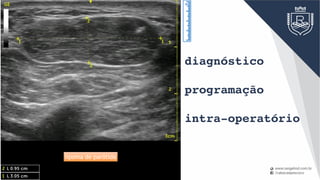

diagnóstico

programação

intra-operatório

Cisto Branquial